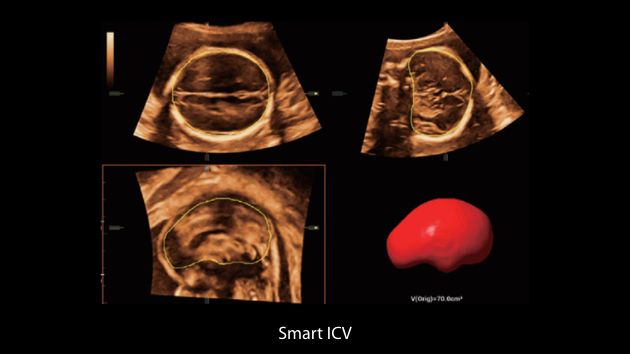

The Nuewa I9, dedicatedly designed for women and neonatal healthcare, providing an innovative experience from inside out.?These innovations are developed based on in-depth insights into complex clinical scenarios, providing accurate and timely answers as well as outstanding efficiency and remarkable user experience.

Clinical Images